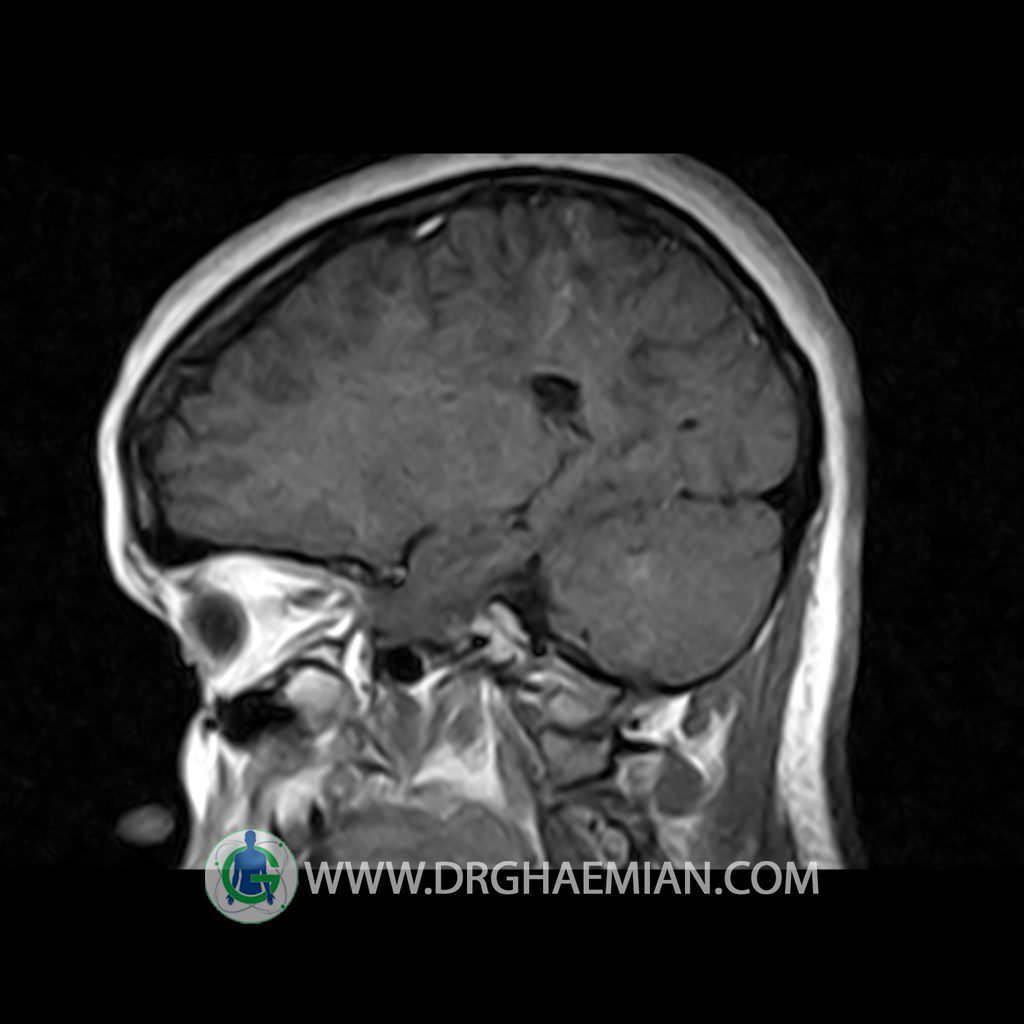

ام آر آی هیپوفیز یک روش تصویر برداری است که از غده هیپوفیز (غده ایی کوچک در مغز که هرومون ها و دیگر غدد بدن را کنترل می کند) و ناحیه های پیرامونش در مغز تصاویری ایجاد می کند. در این کیس سلای نسبتا خالی در ناحیه هیپوفیز بیمار مشاهده می شود.

Technique: Axial , coronal T1 , Axial , coronal , sagittal T2 , Axial, coronal T1 post Gd & 64 dynamic thin coronal slices.

The pituitary tissue shows normal , position, shape , size and homogeneous signal intensity both before and after contrast administration .

The infundibulum is centered and of normal size .

The optic chiasm and suprasellar spaces appear normal .

– Extension of suprasella cistern to sella with thin pituitary gland in floor of sella ( partial empty sella )

is seen